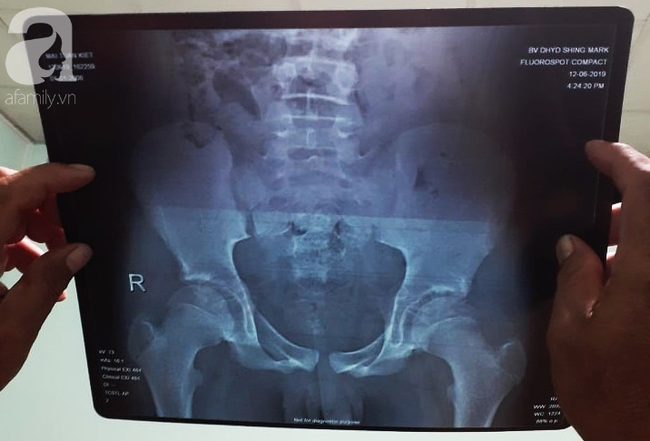

Đến nay, BV có kết luận: vào tối 12/6 bé M.T.K được tiếp nhận từ BV Đại học Y Dược Shing Mark với chẩn đoán gãy trật xương chậu (sau va chạm với xe tải - lời gia đình kể) kèm theo phim X-Quang khung chậu cột sống thắt lưng.

Phim chụp X-Quang của bé K. tại Bệnh viện Đại học Y Dược Shing Mark.

Bác sĩ P.Đ.M. đã chẩn đoán lúc nhập viện là Chấn thương khung chậu phải và chỉ định siêu âm ổ bụng để tầm soát các tổn thương trong ổ bụng. Sau đó bệnh nhi được nằm theo dõi 2 ngày.

Phó Giám đốc Bệnh viện (bìa trái) cho biết bác sĩ chẩn đoán hình ảnh đã ghi nhầm việc bệnh nhân bị gãy xương. Bé chỉ bị tổn thương phần mềm.